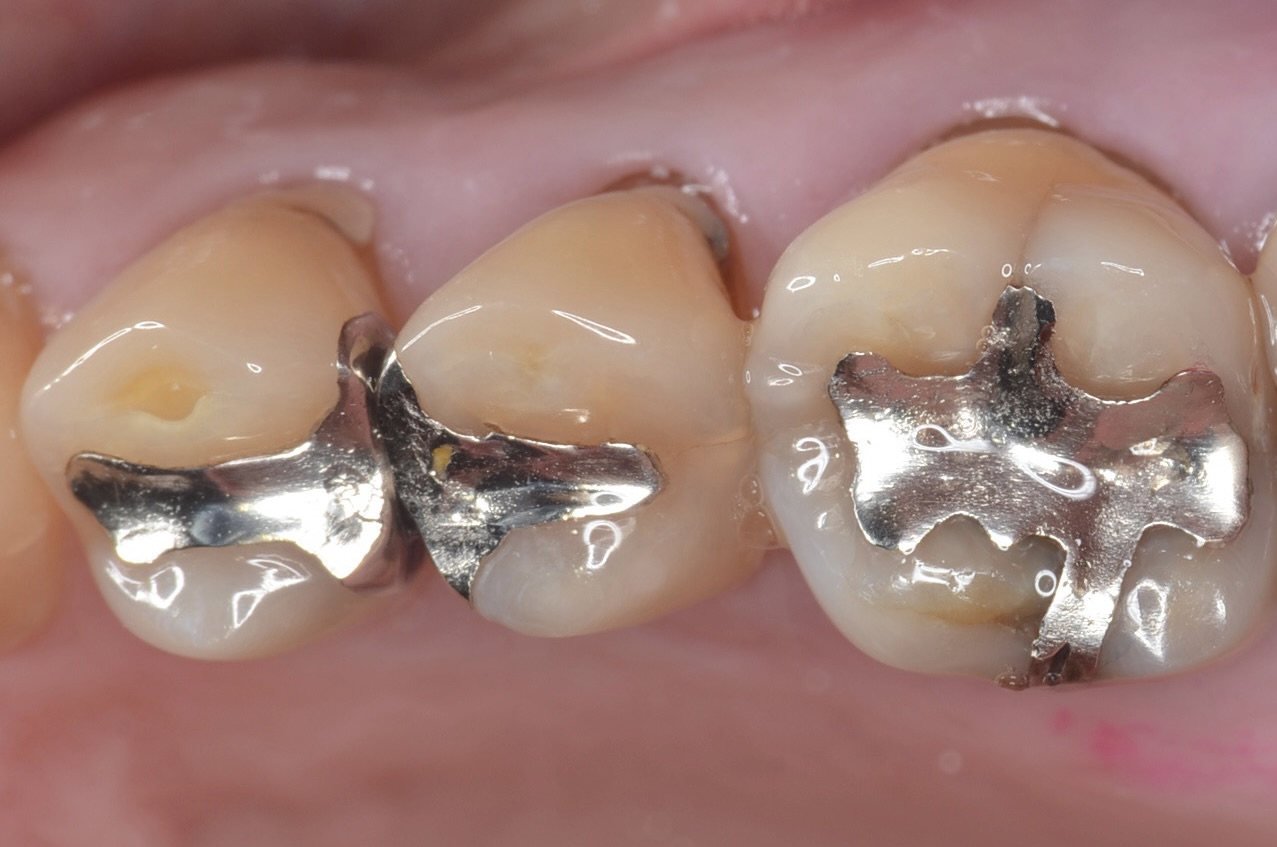

Before

6番のインレーを除去

エナメル質のみを選択的に酸処理をして、接着力を増強させます。 -

6番ダイレクトボンディング

5番遠心

虫歯が広がっていました。 -

6番近心

6番の近親も虫歯でした。 -